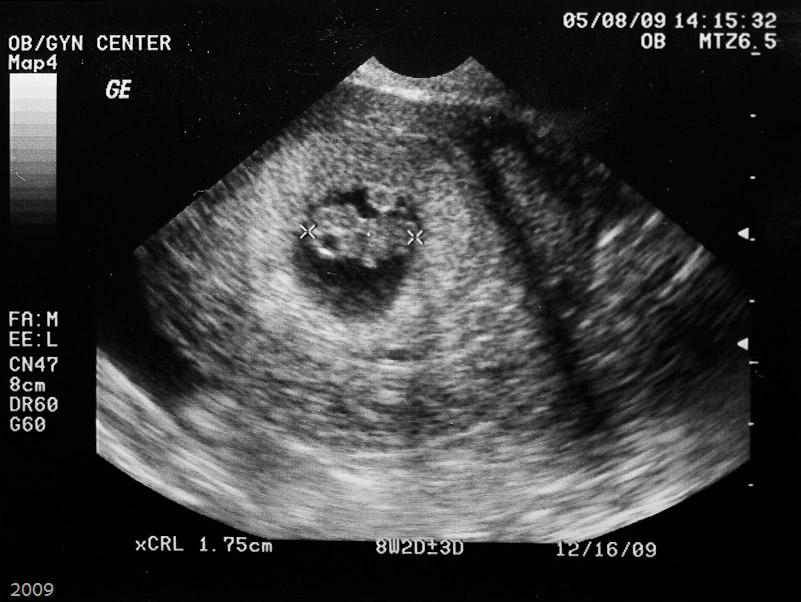

The first ultrasound photo.